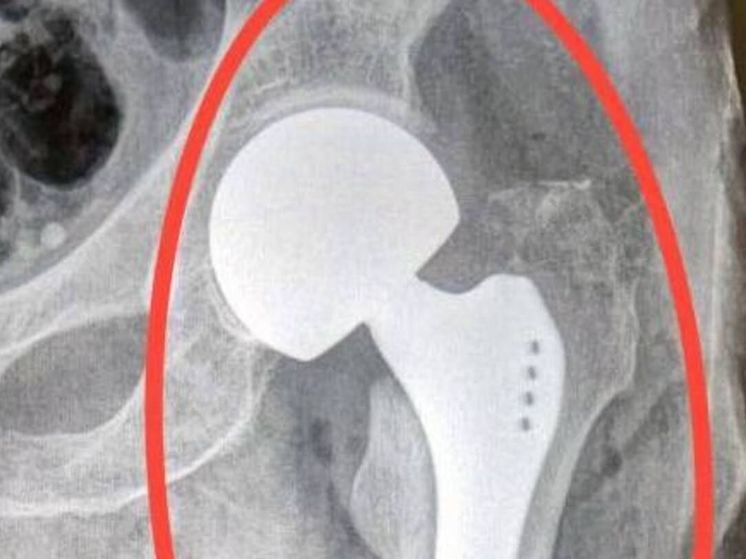

В Подмосковье врачи спасли бабушку 92 лет, которую сбил автомобиль. Сообщает Министерство здравоохранения региона. Женщина пострадала на пешеходном переходе.

В больницу города Долгопрудный ее доставила скорая. Врачи обнаружили у пострадавшей перелом шейки бедра. Необходима была операция. Тазобедренный сустав заменили имплантом.

По данным медиков сейчас подвижность в суставе вернулась. Бабушка, к счастью, чувствует себя уже намного лучше. Ведомство информирует, пациентку выписали домой.